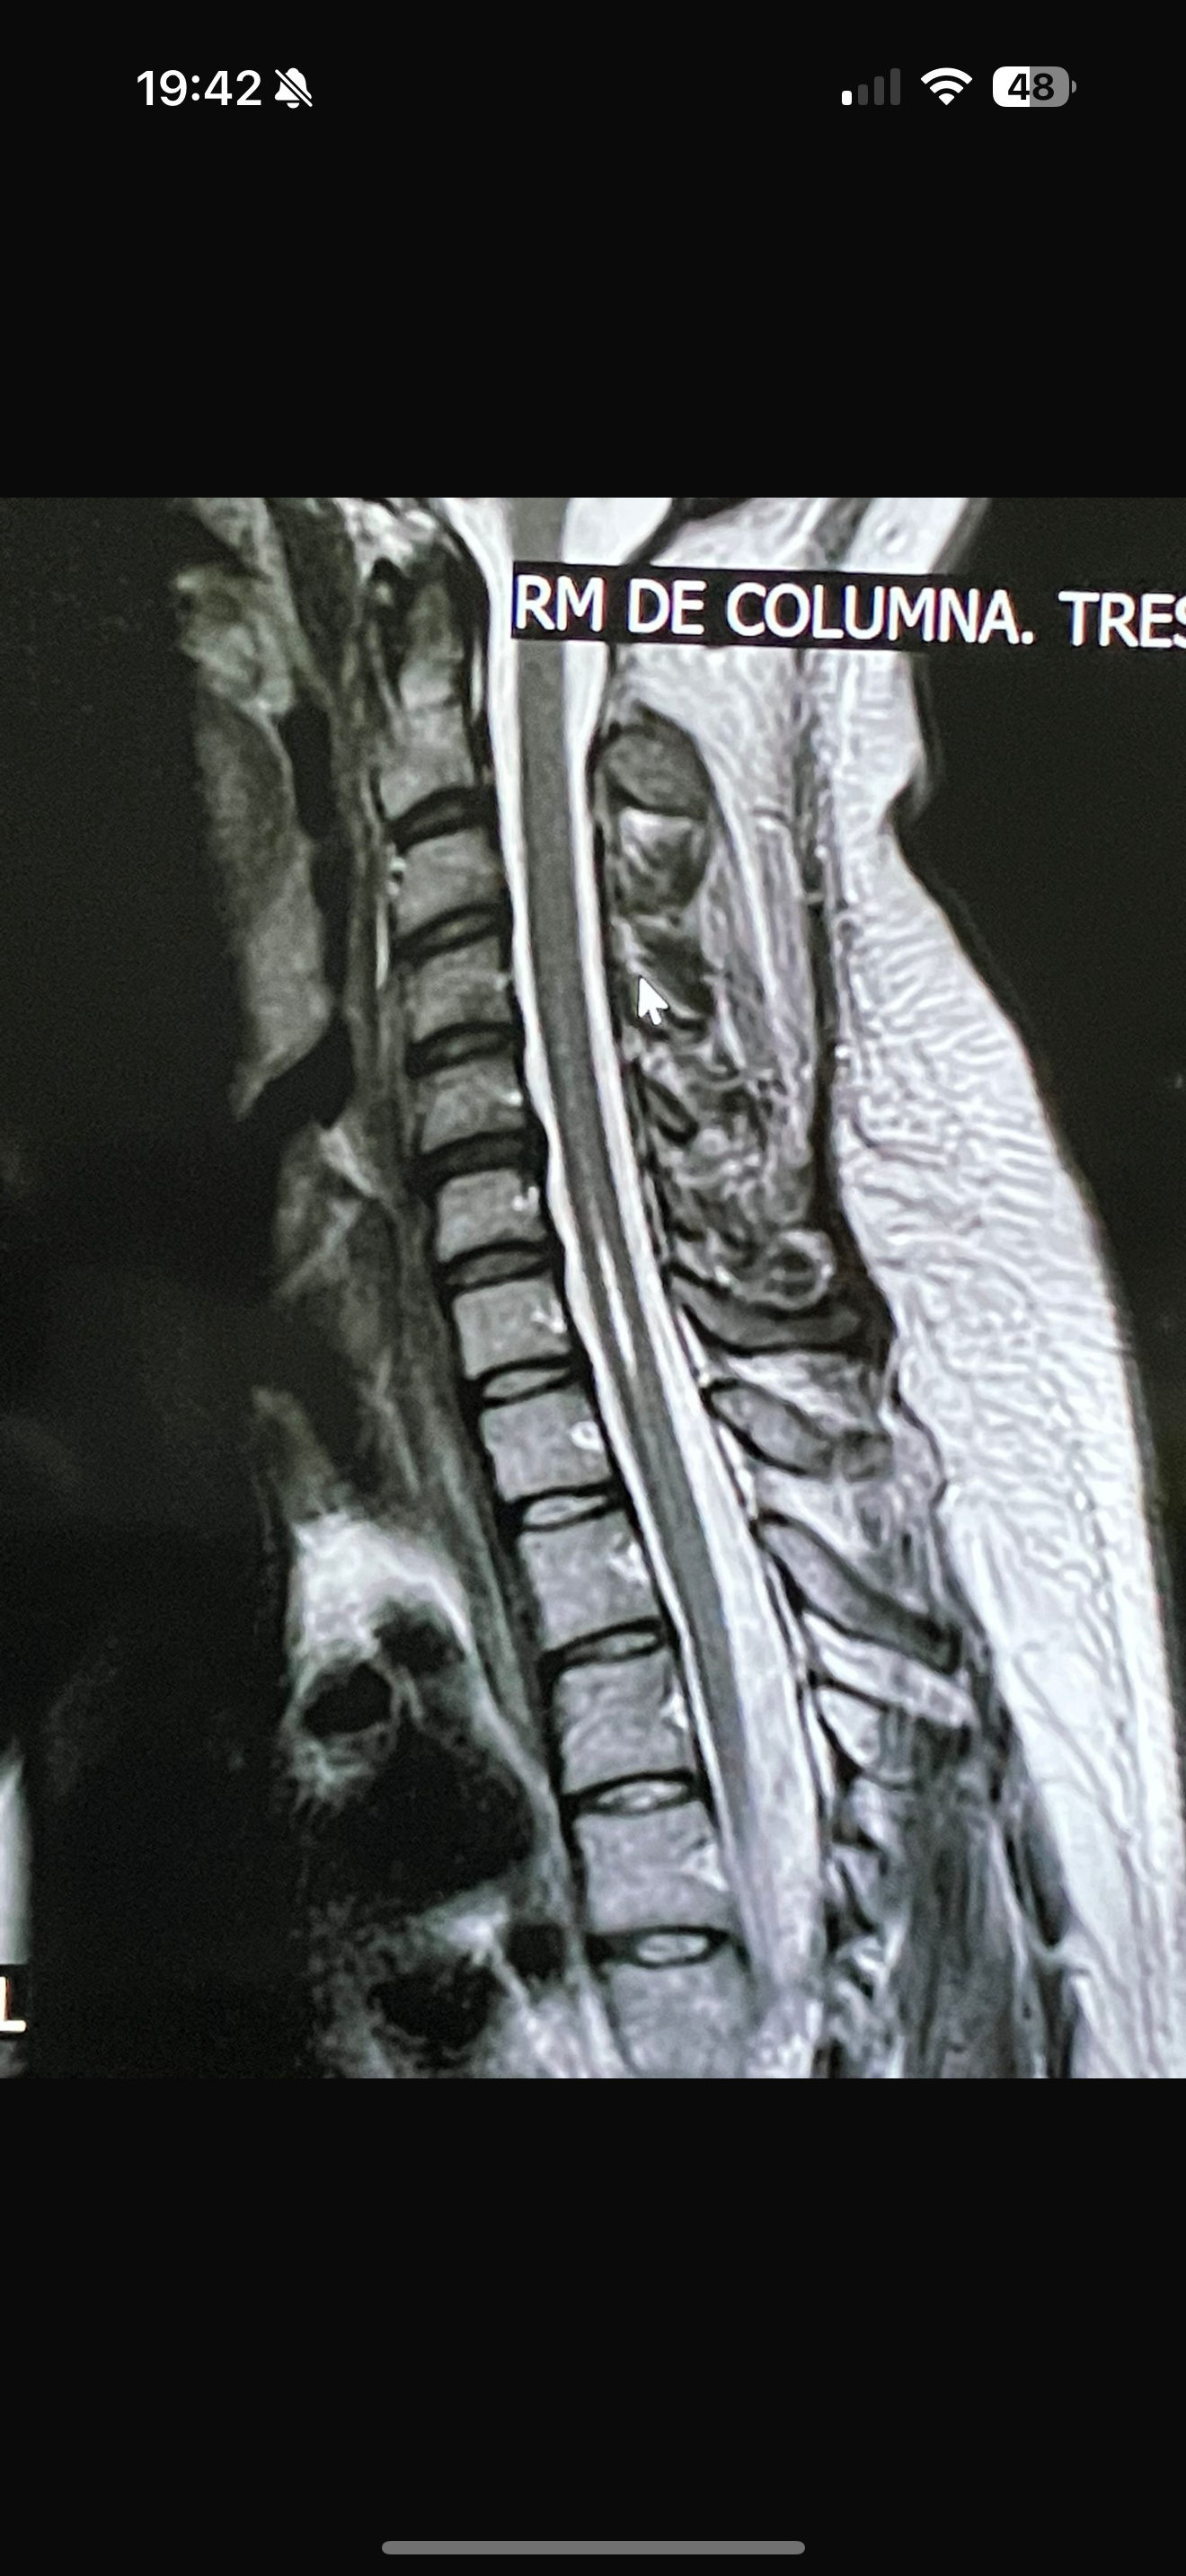

Siringomielia, tengo un quiste en la médula espinal de 2cm de ancho por 2cm de largo que hacen que la mitad izquierda de mi cuerpo esté con problemas de fuerza y sensibilidad, con lo que la mayoría de días debo de usar andador para poder desplazarme.